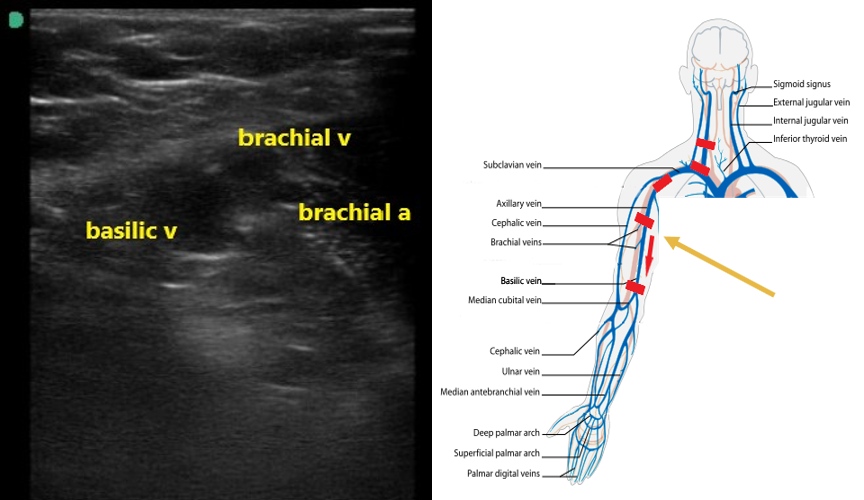

- Upper Extremity Venous Anatomy

- In the neck, around the level of the clavicle, the internal jugular meets the subclavian vein to form the brachiocephalic vein, which in turn flows into the superior vena cava.

- The subclavian vein (SCV) travels beneath the clavicle as the name implies. It is formed by the confluence of the cephalic vein and axillary vein.

- The axillary vein can be found in the proximal medial humeral region in the axilla.

- The axillary vein is formed by the confluence of the brachial vein and the basilic vein.

- Figure 1. Upper extremity venous anatomy (courtesy of Wikimedia)

- The axillary vein going distally will split in the proximal humeral region into the basilic and 2 brachial veins (Fig. 7). The brachial veins will be paired with the brachial artery. The basilic vein is larger, more superficial, and runs medially between the biceps and triceps (Video 3).

- Figure 7. Basilic and brachial veins as well as the brachial artery in the proximal upper arm.